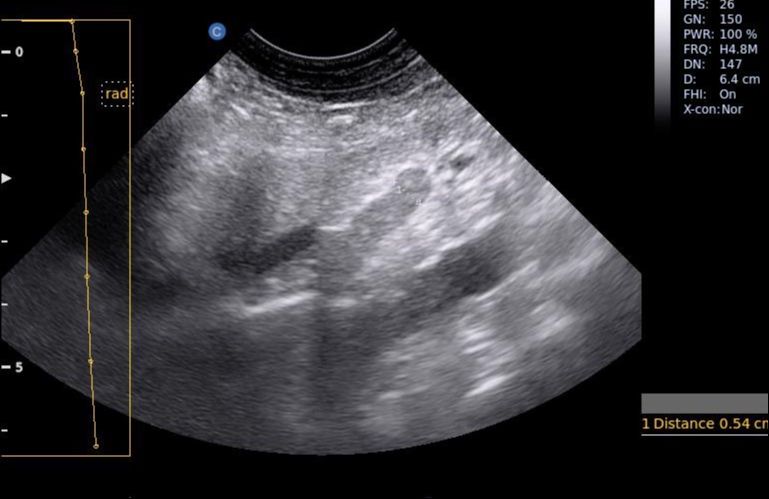

Images from the Ebit30 Vet

It’s not too heavy, not too expensive, decent range of probes to choose from and I found the image quality is good. I should just place a note on the image quality that the Chison imaging can be a bit marmite – you’ll either love it or hate it. The image always appears brighter in recordings than I remember it being at the time, but I’ve found this with other Chison machines too. Having said this, I was able to see all I needed to in the cases I saw during my time with this machine!